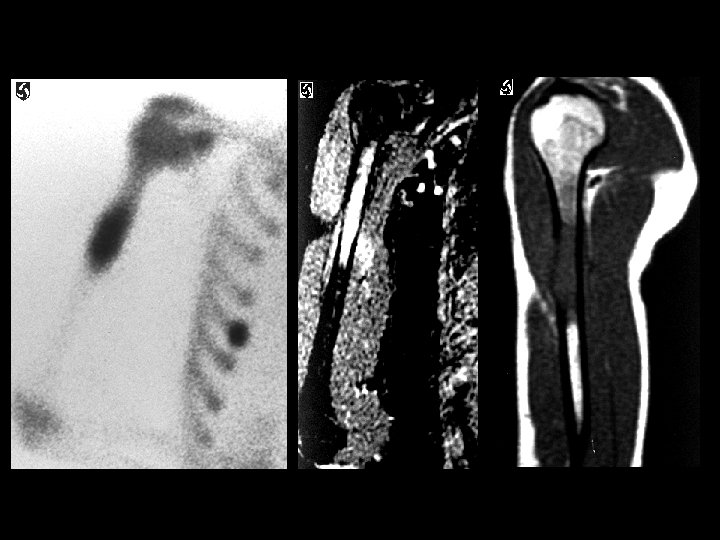

Metastatic Ewing’s sarcoma • Findings: – Intense radiotracer activity in the humeral diaphysis – MR shows an aggressive lesion with cortical disruption and soft tissue edema • ddx: – Lymphoma – Osteosarcoma – Metastasis – osteomyelitis